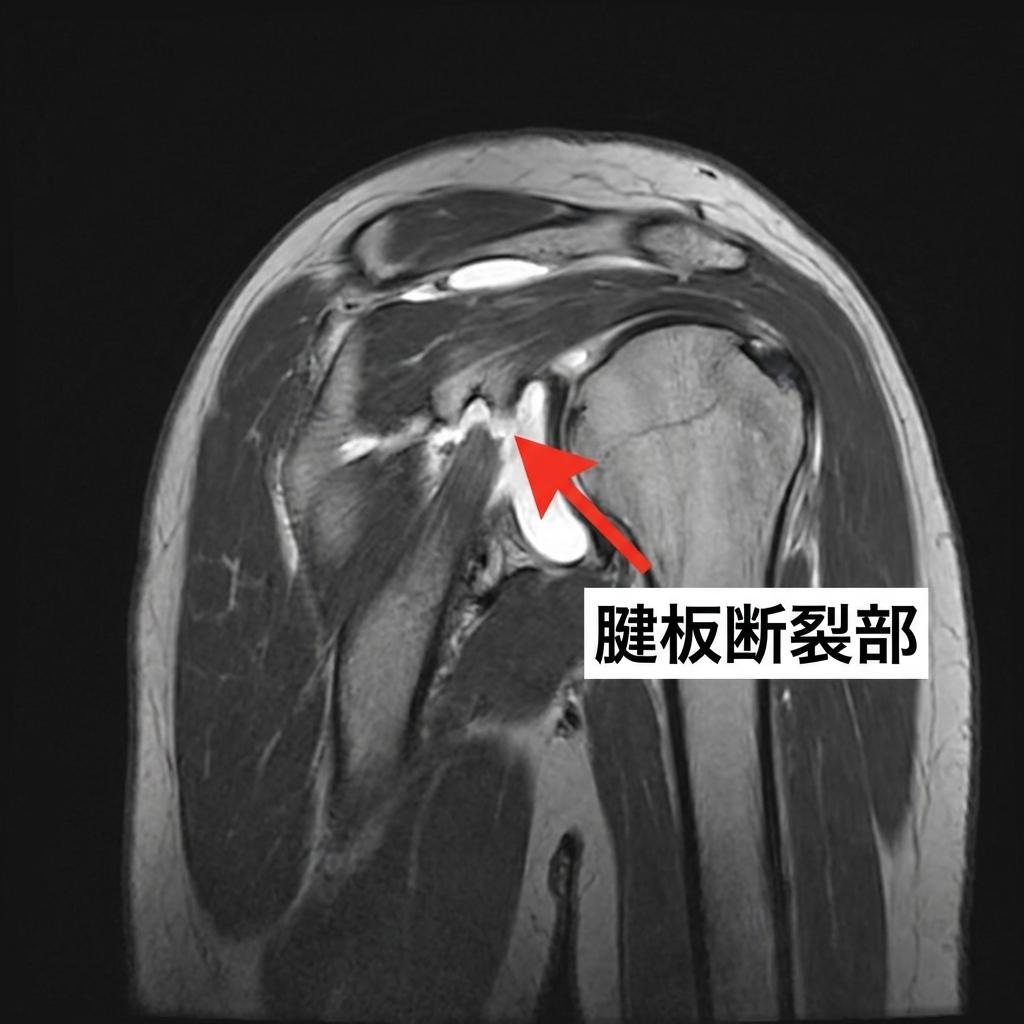

専門医はどうやって診断するの?🏥

- 画像検査: 診断を確定するために、画像検査を行います。

- MRI検査: 腱板断裂の診断において最も精度が高い検査です。断裂の大きさや位置、筋肉の状態まで詳細に評価でき、治療方針を決める上で非常に重要です[2]。